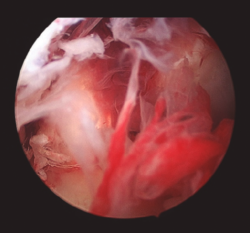

Figura 4. Imagen intraoperatoria artroscópica que muestra el aspecto de la plastia de LCA tras el desbridamiento del tejido sinovial.

También se sugiere eliminar la capa de fibrina que cubre la superficie del injerto y evaluar la integridad macroscópica del injerto, así como su tensión. No es necesario retirar la plastia en todos los casos, debiendo reservarse esta actuación para aquellos casos en los que se objetive un claro fracaso en su funcionalidad, aspecto séptico durante la artroscopia o persistencia de la infección pese al tratamiento correcto(4).